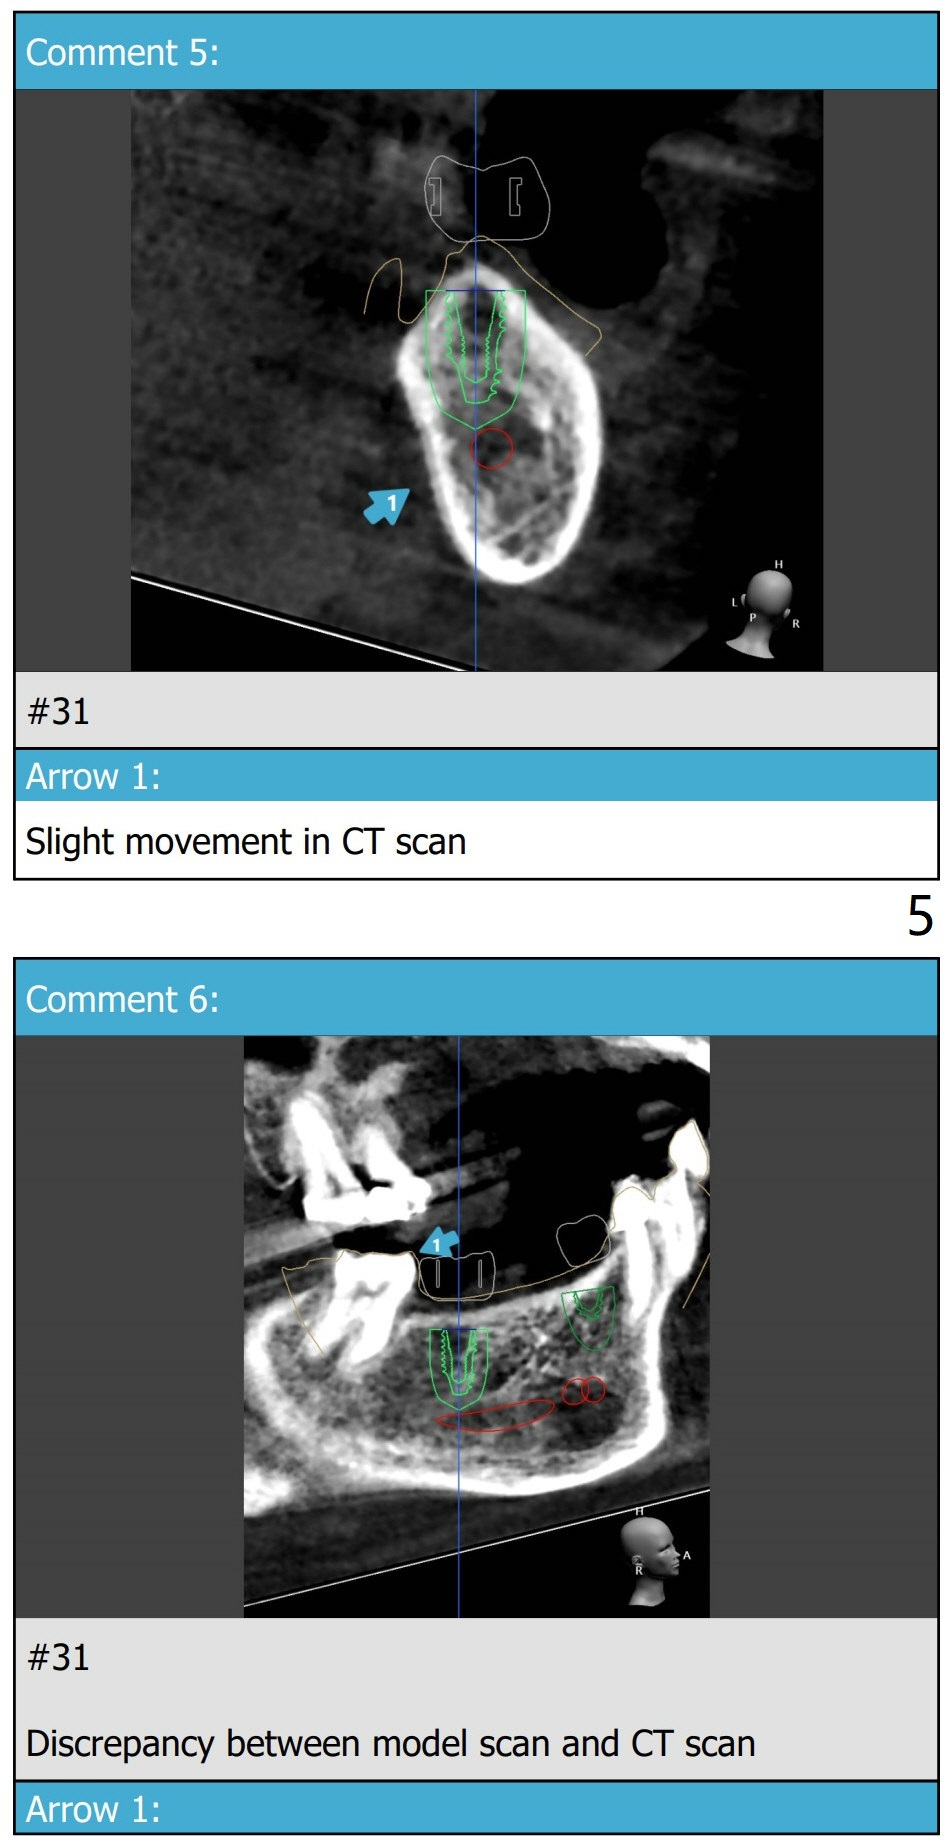

Implant FPD: Design 1

A 81-year-old woman wants to eat well.  #3, 15, 29-31 are missing.